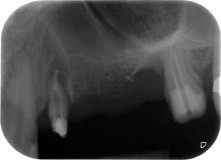

apikale Parodontalläsion an Zahn 24

Abb. 1: Bei einer 58-jährigen Patientin zeigt die Röntgenaufnahme vor der OP eine apikale Parodontalläsion an Zahn 24 und einen horizontalen Knochenabbau im zweiten Quadranten.

Eine 58-jährige Patientin, die auch eine gute Freundin und ärztliche Kollegin ist, beschwerte sich über Schmerzen und erhöhte Beweglichkeit ihres Brückenpfeilers 24. Es lag auch eine parodontale Entzündung vor, mit Taschentiefen von 7 mm mesiobukkal und mehr als 12 mm distal und einer Furkationsbeteiligung dritten Grades. Darüber hinaus zeigte die Röntgenaufnahme eine großflächige apikale Aufhellung am endodontisch (alio loco) vorbehandelten Zahn 24 (Abb. 1).

Ein Jahr zuvor waren die Zähne 25 und 26 vor dem Einsetzen der Brücke aufgrund traumatischer und endoparodontaler Ursachen extrahiert worden. Eine Paro-Endo-Läsion wurde bei unklarer ätiologischer Hauptkomponente für den Zahn 24 diagnostiziert. Die Patientin machte deutlich, dass sie ihre Pfeilerzähne 24 und 27 behalten und keinen endgültigen oder temporären herausnehmbaren Zahnersatz akzeptieren will. Darum wurde vereinbart, alles zu versuchen, beide Zähne, trotz der nach den radiologischen und klinischen Befunden als schlecht einzustufenden Prognose, zu erhalten.

Außerdem wurde die Platzierung zweier verdeckt einheilender Implantate an den Positionen 25 und 26 bei einem chirurgischen Eingriff mit offenem parodontalen Debridement und Wurzelspitzenresektion am Zahn 24 geplant. Aufgrund des vertikalen Knochendefizits im Implantationsbereich wurde auch eine interne Sinusbodenaugmentation geplant.